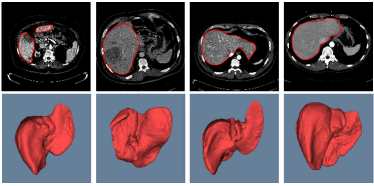

Figure 7: 2D images of segmentation results of four challenging cases in axial, sagittal, and coronal planes with the ground truth in blue. The initial liver region generated by CNNs is in yellow and the final refined result is in red

Figure 8: 3D visual representation of livers segmented by our method on the same four cases as shown in Fig. 7. The first row shows the ground truth; the second and third rows present the surface distance error (mm) of 3D CNNs and the proposed segmentations with the ground truth

Figure 7 illustrates our segmentation and manual delineations for four challenging cases in coronal, sagittal, and axial planes. The initial liver region generated by 3D CNNs is in yellow, the final refined result is in red and the manual delineation is in blue. The first column shows a case with highly inhomogeneous appearances. The last three columns display three representative livers containing tumors. Particularly, some tumors locate on the boundary, which makes it more difficult to automatically delineate the accurate boundary. As can be seen, 3D CNNs can detect the most liver region and the refinement model can obtain a higher agreement with the ground truth. Figure 8 depicts the corresponding 3D visualization results of 3D CNNs and the proposed method for the cases shown in Fig. 7. The 3D visualization of errors is based on the MSD error between the segmentation result and the ground truth. As can been seen, the MSD errors of the 3D CNNs for the four cases (from left to right) are 22.1 mm, 12.6 mm, 62.6 mm and 74.5 mm, respectively, while the MSD errors of the proposed model are 17.0 mm, 11.2 mm, 22.1 mm and 15.3 mm, respectively. Obviously, the proposed approach can obtain lower errors in terms of MSD.